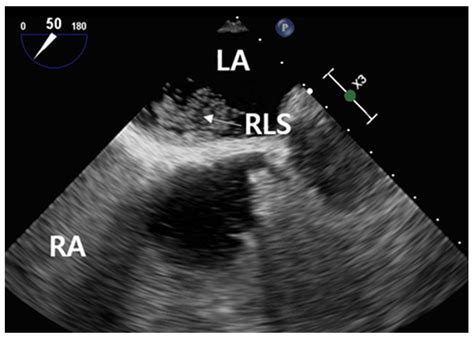

Diagnostic imaging and testing are crucial for confirming the presence and severity of the shunt. Clinicians typically utilize the following tools:

Echocardiography Visualizes blood flow and identifies structural septal defects.

Bubble Study Uses agitated saline to track the movement of bubbles across heart chambers.

⚠️ Note: A bubble study is particularly effective at identifying a PFO or atrial septal defect, as the microbubbles act as a contrast agent that can be easily visualized crossing the septum on an echocardiogram.